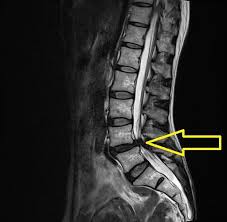

脊柱管狭窄症とは、脊髄の通り道である脊柱管が狭くなることで神経が圧迫され、痛みやしびれが生じる疾患です。脊柱管は脊椎によって形成されるトンネル状の空間で、脊髄や神経根が通っています。加齢や変性によって骨や靱帯が肥厚し、脊柱管が狭くなることが一般的な原因です。症状は部位によって異なりますが、腰部に発生することが多く、主な症状としては腰痛、足のしびれや痛み、歩行困難(間欠性跛行)などがあります。

脊柱管狭窄症の主な原因は、加齢による脊椎の変性です。椎間板のすり減りや、椎間関節の肥大、靱帯の肥厚が進行し、脊柱管が狭くなります。また、外傷や先天性の要因、骨の病変が影響することもあります。特に60歳以上の高齢者に多く見られますが、若年層でも外傷や特定の疾患により発症することがあります。